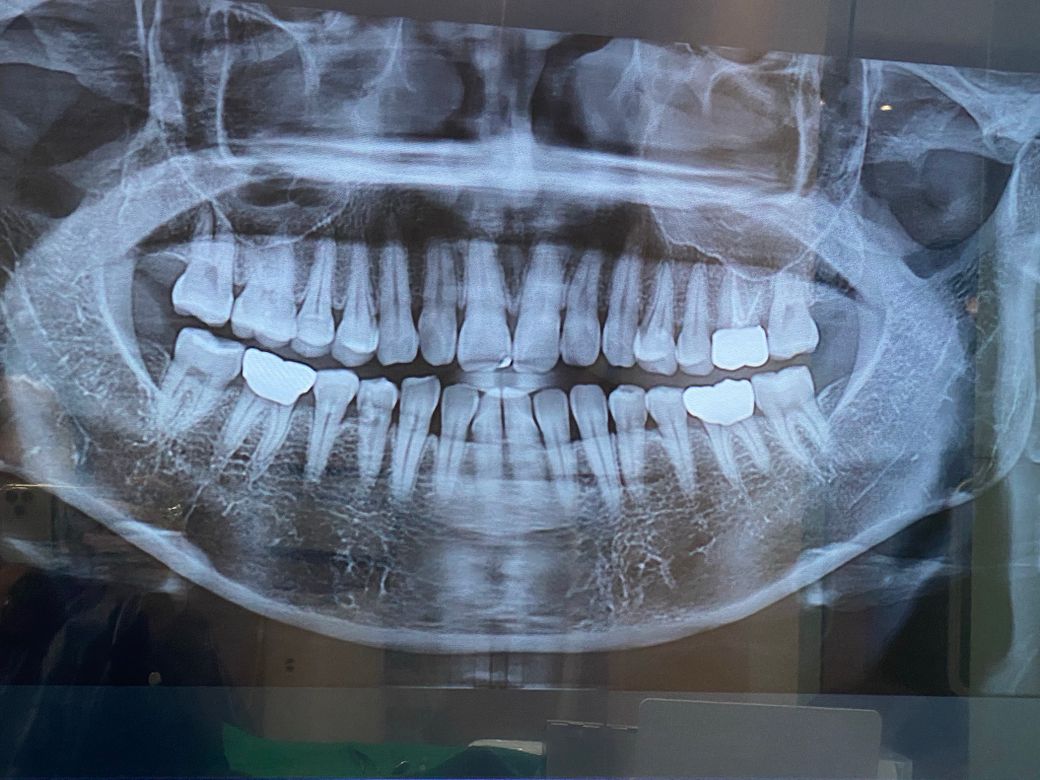

크라운제대로부착된게맞을까요??

이번에 어금니를 싹다 인레이 크라운을씌웠는데요

왼쪽위 크라운은 신경치료하고 씌운날부터 계속 먼가

불편해여 아프거나 시린증상은 없는데

크라운을 최종부착할때 찌지직소리가 났었거든요

그것때문에 안에 이빨이 먼가 잘못된건지

계속 잇몸주변에 치실할때마다 피나고

아쿠아픽할때마다 피나고 혀로 퉁퉁밀면 먼가 내이빨같지않은 느낌에 암튼 계속 거슬리는데

의사쌤은 크라운도 잘붙여졌고 이상이 없다는데

그리고 오른쪽위 어금니 76인레이

오른쪽 아래 6신경치려안하고 크라운

5 인레이를 했는데

교합조정을 받고나서 너무 낮아졌는지

오른쪽앞니가 닿아서 얼얼한데

어떻게 조취를 취해달라고 해야할까요??

아래 6번 크라운을 다시 뜯고 높이맞춰 다시재제작?

아님 위 인레이 뜯고 다시 재제작??

교합이 안맞으니 턱도 아프고 광대도 아프고

머리까지 아픕니다

돈은 몇백쓰고 이렇게 불편하게 살아야 하나요??

• 1번 째 사진